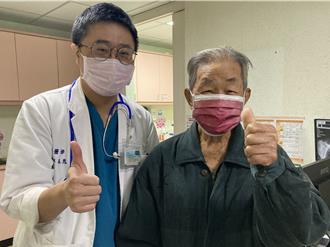

心臟跳不動險昏厥 「膠囊節律器」助9旬翁恢復心律

台中市92歲王姓老翁近日出現胸悶、頭暈、氣喘、心跳過慢,甚至連坐著都會暈眩,於是緊急就醫後,發現其心臟每分鐘跳動少於40次過慢,經醫師採用「膠囊心臟節律器」,才讓王翁跳次數趨於穩定。